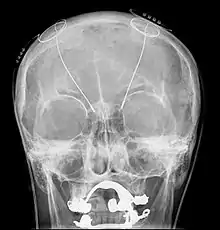

Корональний розріз головного мозку одразу навпроти мосту Субталамічне ядро позначене як "Nucleus of Luys" (ядро Люїса).

Глибока стимуляція мозку - Deep brain stimulation (DBS) з установленням "мозкового водія ритму". На рентгенограмі видні встановлені електроди